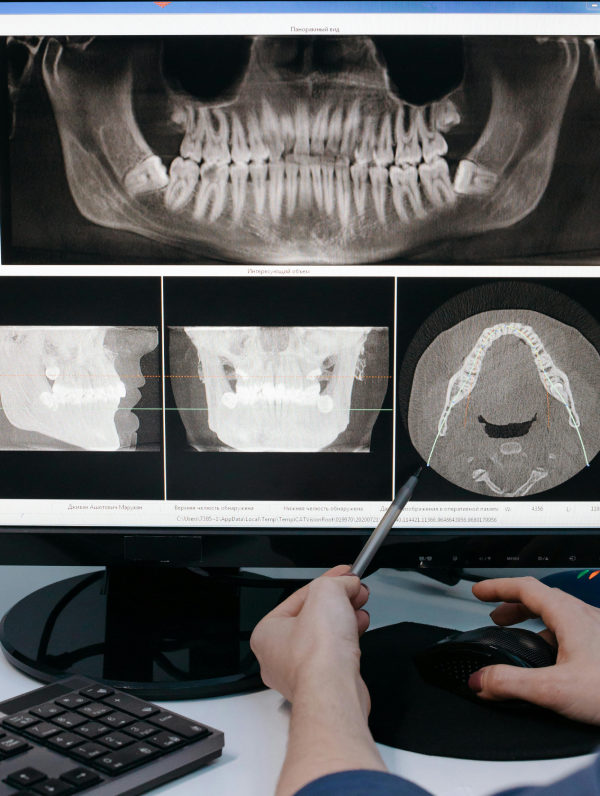

Κατά τη διάρκεια της ορθοπαντομογραφίας, ο ασθενής τοποθετείται κάτω από το μηχάνημα και το ακτινολογικό μηχάνημα κινείται γύρω από το κεφάλι, λαμβάνοντας την εικόνα από διάφορες γωνίες. Ο οδοντίατρος ή ο ακτινολόγος θα σας ζητήσει να παραμείνετε ακίνητοι για λίγα δευτερόλεπτα, ενώ το μηχάνημα καταγράφει την εικόνα. Η διαδικασία είναι γρήγορη, διαρκεί μόλις μερικά λεπτά, και είναι ανώδυνη.